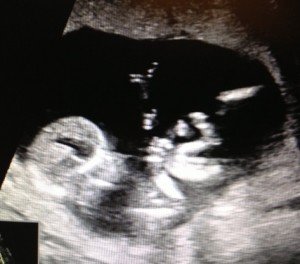

Meet said human: 13 week ultrasound

At 13 weeks, it looks more like a human, and Jesse and I just sat there with a goofy ass grin on our faces watching it roll and bounce all over the place. It's the size of a peach. P.S. Why are all the standard size comparisons for babies food-related?